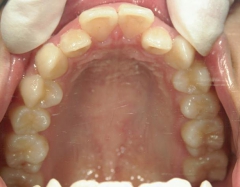

矯正_灰色.pngno.18_2196_治療前_上.jpg矯正_灰色.png

矯正_灰色.pngno.18_2196_治療後_上.jpg矯正_灰色.png